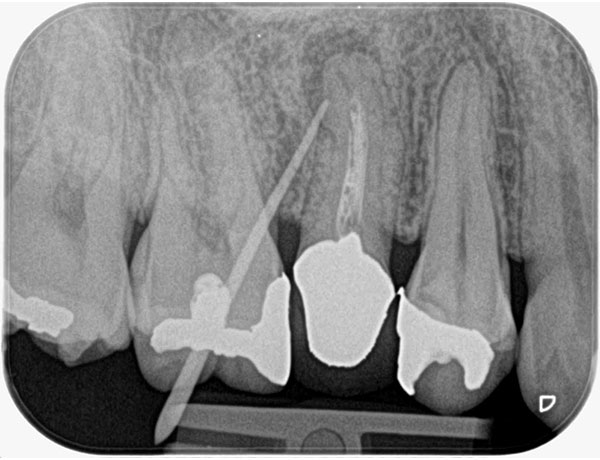

主訴: 噛むと痛い、奥歯が違和感ある

保険治療では発見することが難しい4つ目の神経を

歯を大きく削らずに見つけられます。